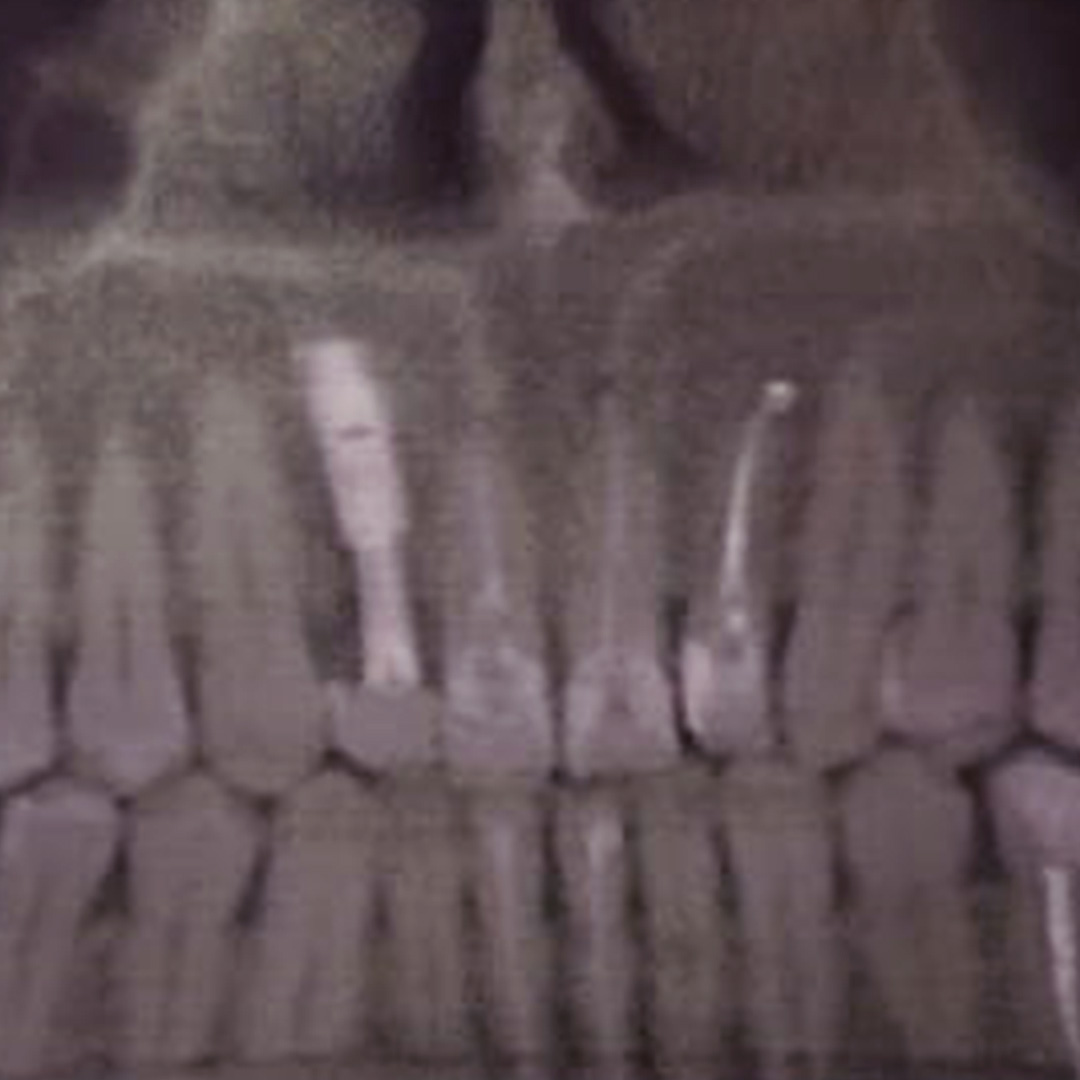

До и после лечения

Пациентка обратилась в «Стоматологию Комфорта» с жалобами на периодические ноющие боли в зубе 1.2. Врач Тарасов Денис Геннадьевич провёл обследование и поставил диагноз — хронический периодонтит верхнего резца. Проведено удаление зуба с одномоментной имплантацией.

- проведение одномоментной имплантации;